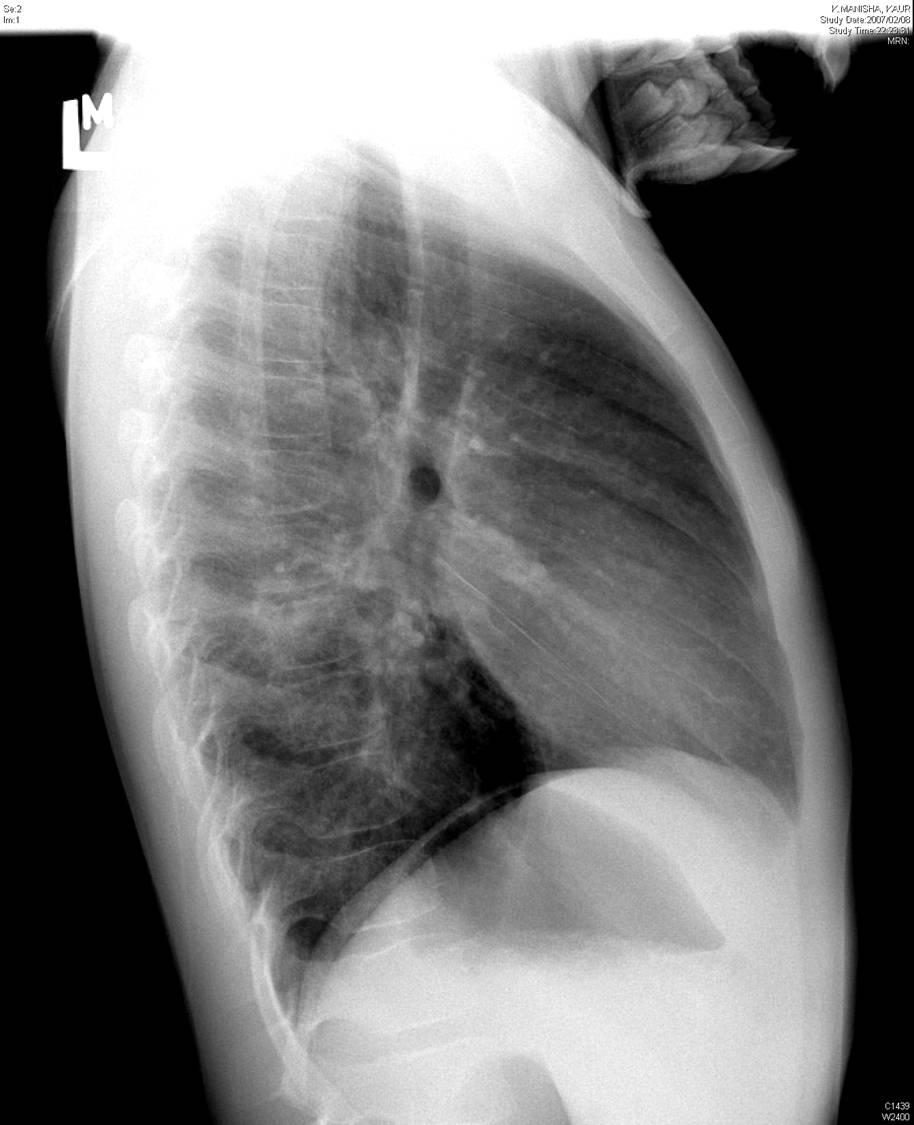

A chest x-ray from local hospital was reviewed

| Figure 1-a | Figure 1-b |